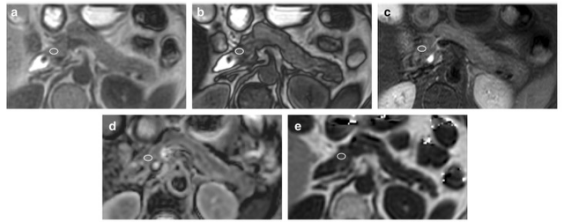

圖 66 歲女性,胰腺正常組脂肪肝。 感興趣區域 (ROI) 的測量在胰腺頭部進行軸位同相位成像 (a)、軸位反相位成像 (b)、軸位 T2 加權成像 (T2WI) (c)、軸位表觀擴散系數 (ADC) 圖 (d) 和軸向多回波 3D DIXON (e)